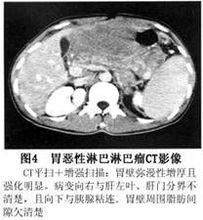

(3)CT檢查:可進一步了解腫塊部位、範圍、大小、胃周圍淋巴結有無腫大以及鄰近臟器有無占位病變和肝、脾是否腫大。

4.灰階超聲和CT檢查 可見胃壁呈結節狀增厚可確定病變的部位範圍以及對治療的反應。表現為腹部腫塊的胃淋巴瘤,超聲檢查可助診斷。